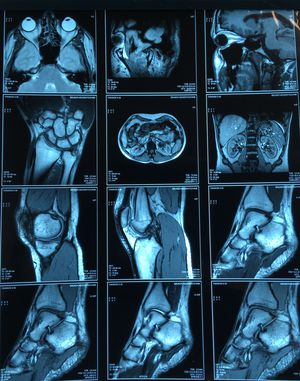

MRI or CT?

MRI

MRI, CT images are less defined. MRI is like looking through a specialist anatomy textbook